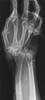

Four days ago 40 y/o female suffered in MVA. She was pedestrian and was droven over by drunken driver. She hooked underneath the car and was dragged by car 498.5 meters (police data). She got a severe friction of right wrist and arm, friction of face, left orbital fracture and both thigh and abdominal burns of III degree, about 10% caused by hot exhaustion pipe, also some friction burns.

At presentation arm debridgement was done and wrist was stabilized with 3 K-wires. There was complete loss of extensor tendons, distal third of dorsal pole of radius was grated away, proximal row of carpals was almost gone, loss of fifth MC and half of fourth MC.